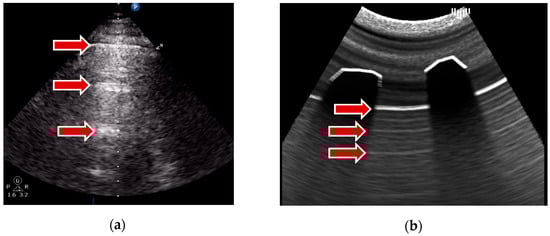

A-lines are horizontal, parallel lines seen in normal lung tissue and are created by the multiple reflections of ultrasound waves between the pleural line and the transducer. This is achieved during the ray marching step without a time-consuming ray generation: the input frame buffer, which stores the image of the first render pass, is repeatedly sampled relative to the distance of a pleural line to the transducer. The results can be seen in Figure 3.

Figure 3. A-lines example: (a) real examination; (b) the LUS simulation.